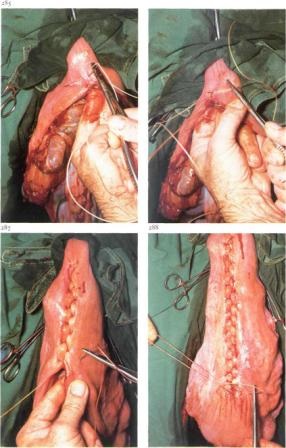

uterină de scurgere cavitatea tifon steril. Uterine rănii margini cusute cusătură decker: mai întâi prin Shmidenu ( „spic“ cusătură continuă tinuous toate secțiunile uterului), iar al doilea Lambert (joint sero-muscular). Așa cum catgut sutura utilizat № 6-8. In cererea sa G. Merkt fertilizarea atins 83% din vacile operate, în timp ce coaserea uterului după celelalte margini ale materialului de sutura plăgii - doar 43%.

Rana a fost suturată de perete cu trei etaje metoda cusătură suprapusă abdominală este diferit și depinde de locul de acces rapid. Cu un mediu de acces al primului cusătură continuă catgut № 8 strânsoare peritoneu, fascia lateral mușchiului oblic transversal intern și mușchi abdominal. Al doilea înnodat sutura de catgut № 10 este suprapus pe fascia abdominală galben și mușchiul oblic extern. A treia înnodat sutura matase № 10 conectați marginile unei răni de piele, unge-l cu soluție de iod și se acoperă bandaj adeziv.